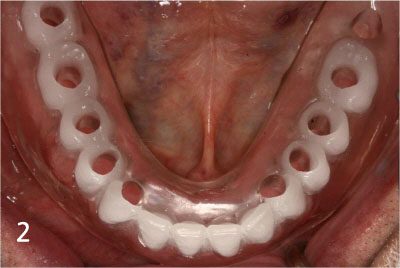

Totally edentulous status on lower jaw

Fit surgical guide for precise implant placement

Removal of gum at exact site for implant placement with dental laser

Placing Implants

Connection of temporary cylinder for provisional bridge

Provisional bridge to use right after placing implants

This is after bonding provisional bridge. Patient can have strong teeth in a few hours